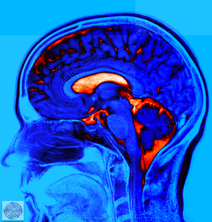

Das seitliche Bild des Gehirns im MRT

Gehirn in voller Schönheit

Unser Schaltzentrum ist ein Meisterwerk. Auch wenn wir es besitzen, können wir etwas Ähnliches bisher nicht nachbauen. Immense Rechenleistung und enorme Speicherkapazität. Wir machen dieses Wunder im MRT sichtbar und können kleinste Schäden diagnostizieren, um eine Therapie möglich zu machen